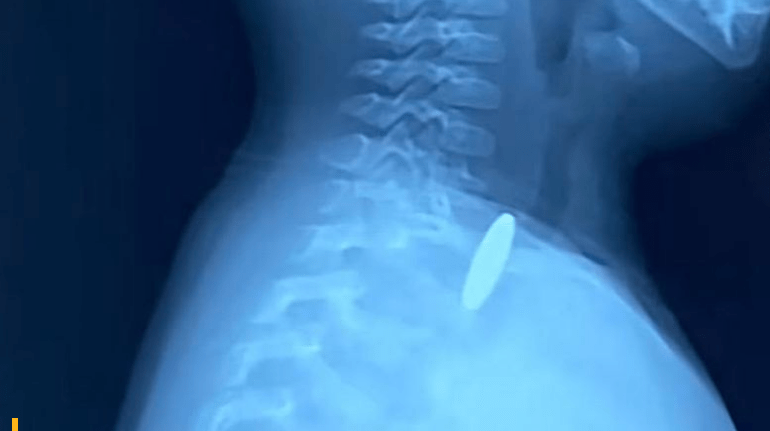

Είχε καταλάβει ότι ο βήχας του παιδιού, έμοιαζε με τον βήχα που είχε όταν πνιγόταν από κάτι. Τους εξήγησε λοιπόν πως θέλει να σιγουρευτεί πως δεν έχει κολλήσει κάτι στον οισοφάγο του. Η μητέρα είχε δίκιο! Στην ακτινογραφία οι γιατροί είδαν ένα στρογγυλό αντικείμενο σφηνωμένο στον οισοφάγο του.

Μάλιστα οι γιατροί αποφάσισαν να προχωρήσουν σε χειρουργείο διότι από την ακτινογραφία δεν μπορούσαν να καταλάβουν αν πρόκειται για κέρμα ή κάποιο άλλο στρογγυλό αντικείμενο ή για τοξική στρογγυλή μπαταρία.